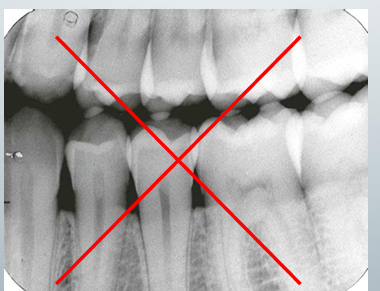

bad BW view

-wrong horizontal angulation → contacts overlap

-cannot evaluate the interproximal caries